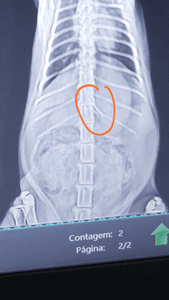

Semana passada meu gato comeu uma agulha, estamos torcendo pra ele continuar bem

a cirurgia está muito cara mas muito necessária